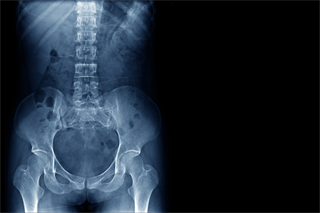

L’Ecografia è una metodica diagnostica non invasiva che utilizza ultrasuoni per valutare in tempo reale organi e tessuti senza esposizione a radiazioni ionizzanti.

L’esame consente di rilevare alterazioni anatomiche, infiammazioni, lesioni o patologie vascolari e cistiche, fornendo informazioni fondamentali per la diagnosi precoce e il monitoraggio di patologie acute e croniche.